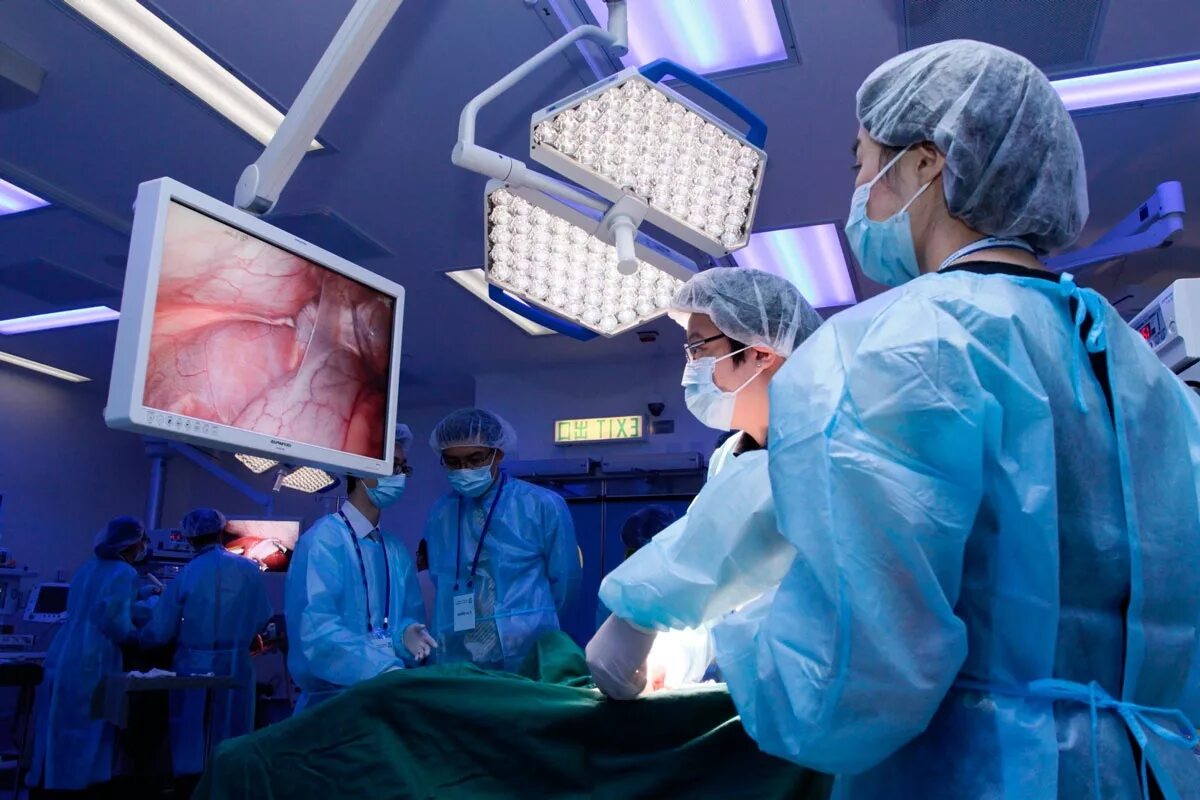

Филлоидная фиброаденома молочной железы УЗИ. УЗИ признаки доброкачественных опухолей молочных желез. Доброкачественная опухоль молочной железы на УЗИ. Опухоль молочной железы на УЗИ. Хирургическая операция. Эндоскопическая операция. Хирургическое вмешательство. Эндоскоп хирургический.

Хирургическая операция. Эндоскопическая операция. Хирургическое вмешательство. Эндоскоп хирургический. Периферическая карцинома легких кт. Периферический очаг легкого. Кт признаки периферического. Периферическое новообразование.

Онкомаркеры локализация опухоли. Онкомаркеры презентация. Онкомаркеры в онкологии. Анализ на онкомаркер. Нейроэндоскопия головного мозга. Хирургическая операция на головном мозге. Эндоскопические операции на головном мозге. Хирургическое вмешательство в мозг.

Нейроэндоскопия головного мозга. Хирургическая операция на головном мозге. Эндоскопические операции на головном мозге. Хирургическое вмешательство в мозг. Магнито-резонансная томография молочной железы. Маммография дуктография. Фиброаденома молочной железы кт. Опухоль молочной железы мрт.